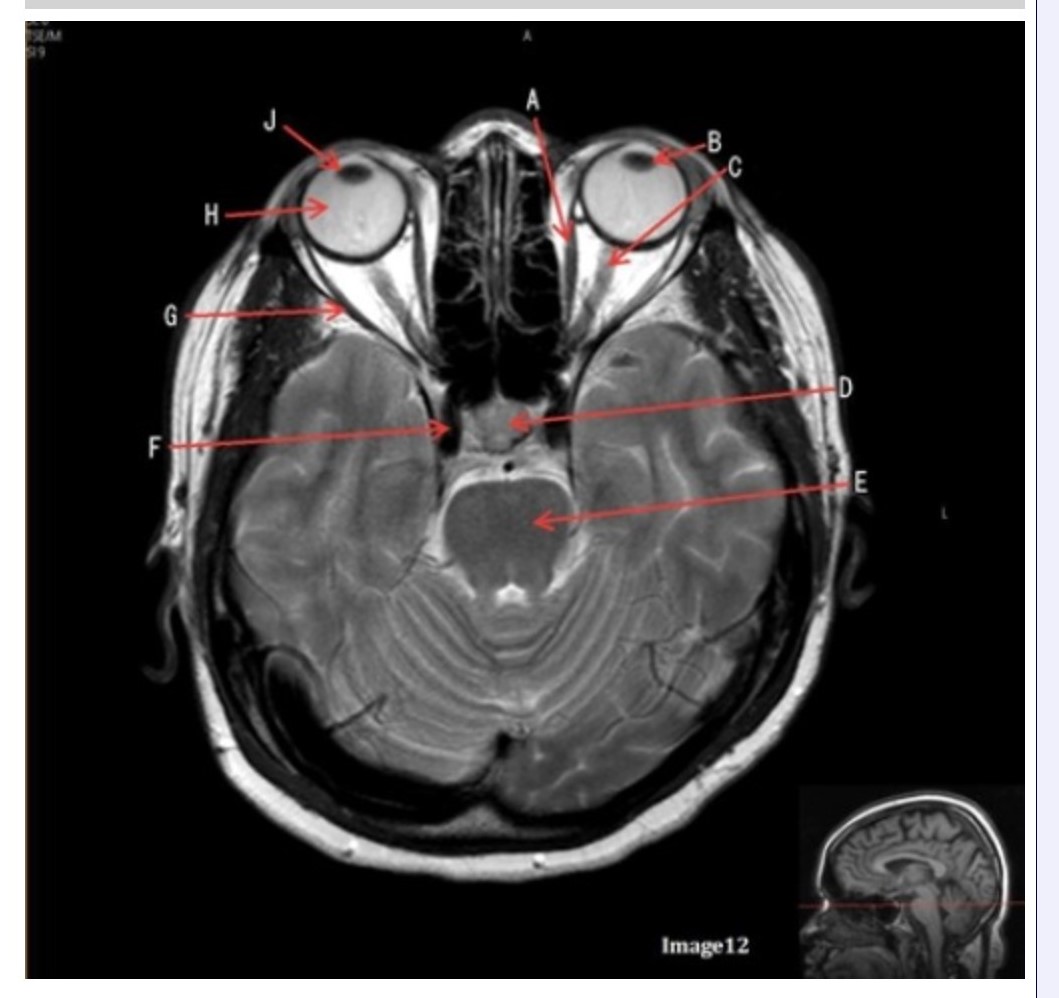

Letter H in Image 12 is pointing to:

A. Lens

B. Lateral rectus muscle

C. Medial rectus muscle

D. Internal carotid artery

E. Globe

Letter B in Image 12 is pointing to:

A. Left optic nerve

B. Lateral rectus muscle

C. Medial rectus muscle

D. Lens

E. Midbrain

Letter J in Image 12 is pointing to:

A. Globe

B. Lateral rectus muscle

C. Medial rectus muscle

D. Right lens

E. Left lens

Letter F in Image 12 is pointing to:

A. Lens

B. Lateral rectus muscle

C. Medial rectus muscle

D. Internal carotid artery

E. Globe

Letter C in Image 12 is pointing to:

A. Left optic nerve

B. Lateral rectus muscle

C. Medial rectus muscle

D. Lens

E. Midbrain

Letter D in Image 12 is pointing to:

A. Optic nerve

B. Pituitary gland

C. Globe

D. Lens

E. Midbrain

Letter G in Image 12 is pointing to:

A. Lens

B. Lateral rectus muscle

C. Medial rectus muscle

D. Internal carotid artery

E. Globe

Letter E in Image 12 is pointing to:

A. Optic nerve

B. Pituitary gland

C. Globe

D. Pons

E. Left lens